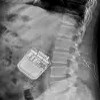

Коррекция положения спинальных электродов

Коррекция положения позвоночных электродов. Хирургическая процедура для изменения положения первоначально установленного электрода. Необходимы неудовлетворительные результаты периода испытаний, при смещении или миграции электрода, сопровождающемся исчезновением анальгетического эффекта электронейростимуляции. Относится к техническим осложнениям после имплантации. Положение электрода выясняется рентгеновским излучением. Во время повторной операции проводится ревизия системы нейростимуляции, чтобы найти оптимальное положение для электродов и их надежную фиксацию, а также устранить возможные отклонения.